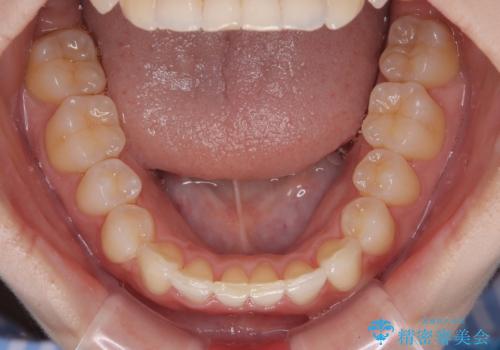

マウスピース矯正特有の、奥歯が噛みにくくなるという現象の解消に少し期間をいただきましたが、日々の装着時間を遵守していただき、綺麗な歯列に整えることができました。